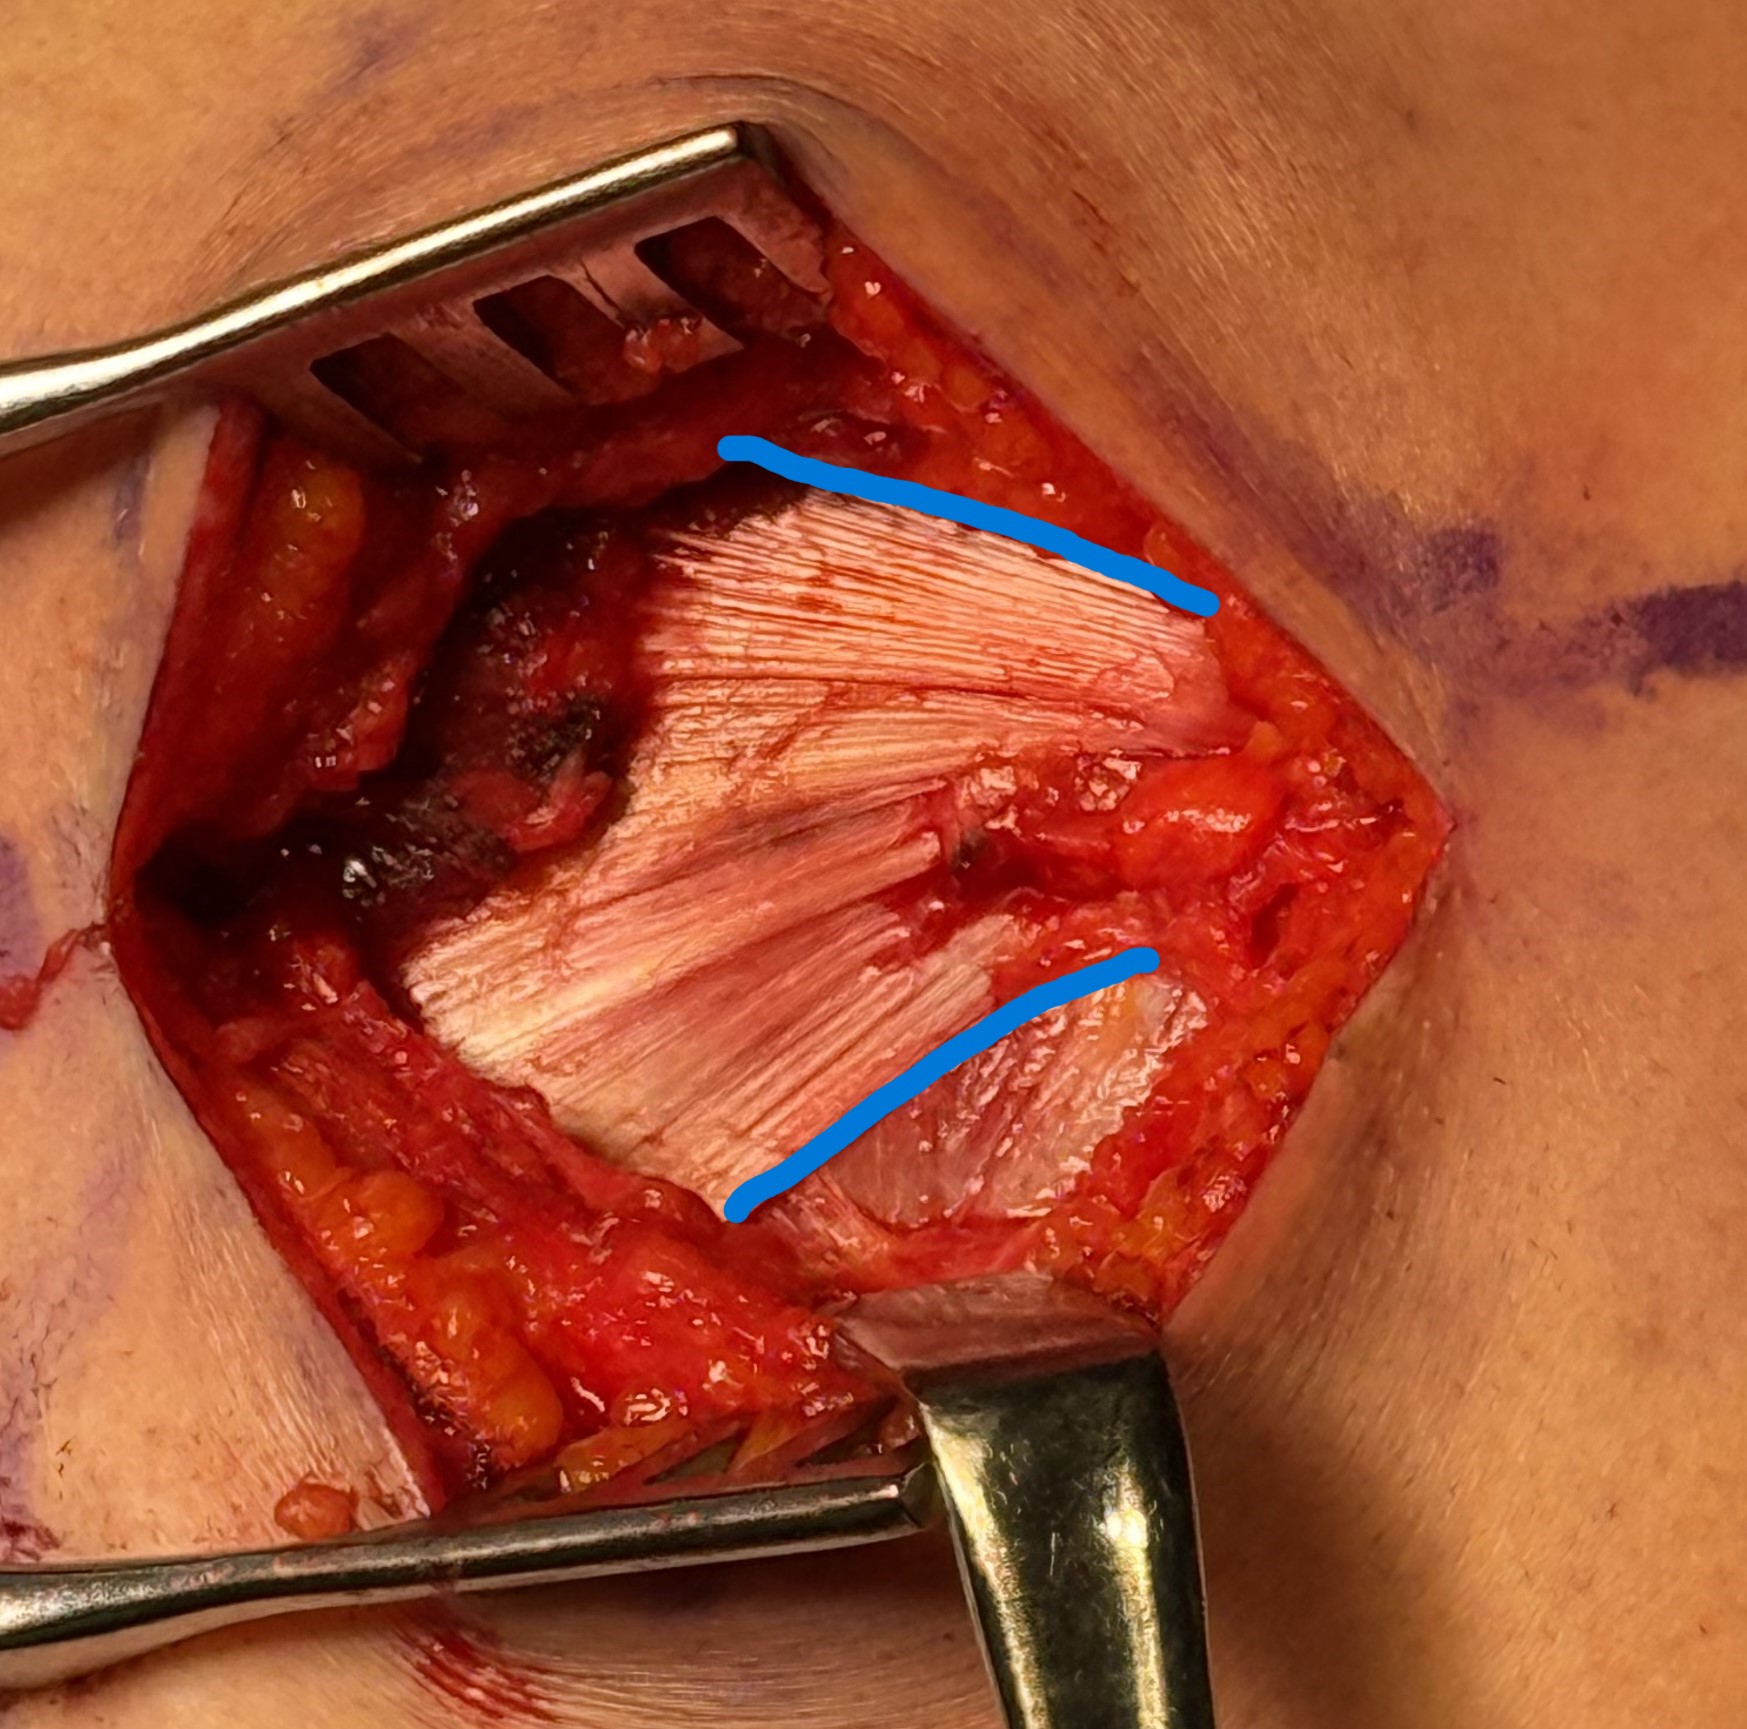

Technique

Margin convergence sutures

Release infraspinatus tendon posteriorly and assess mobility

Repair infraspinatus with a combination of margin convergence and posterior suture anchors onto posterior greater tuberosity

True partial repair of the rotator cuff with exposed triangle of greater tuberosity